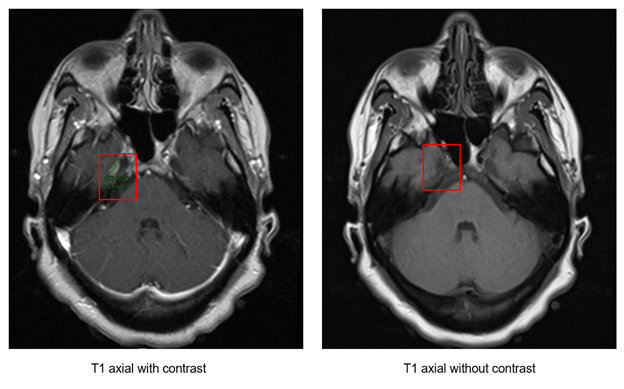

Clinical History: A female in her 5th decade with a past medical history of migraines presented to the emergency department with worsening of chronic left-sided headaches associated with nausea, photophobia, phonophobia, and vision changes.  MRI of the brain demonstrated multiple enhancing extra-axial lesions measuring up to 1.5 cm in greatest dimension (Figure 1). The patient underwent craniotomy for biopsy and excision.

Figure 1: MRI of the brain showing an enhancing extra-axial mass (highlighted in red).